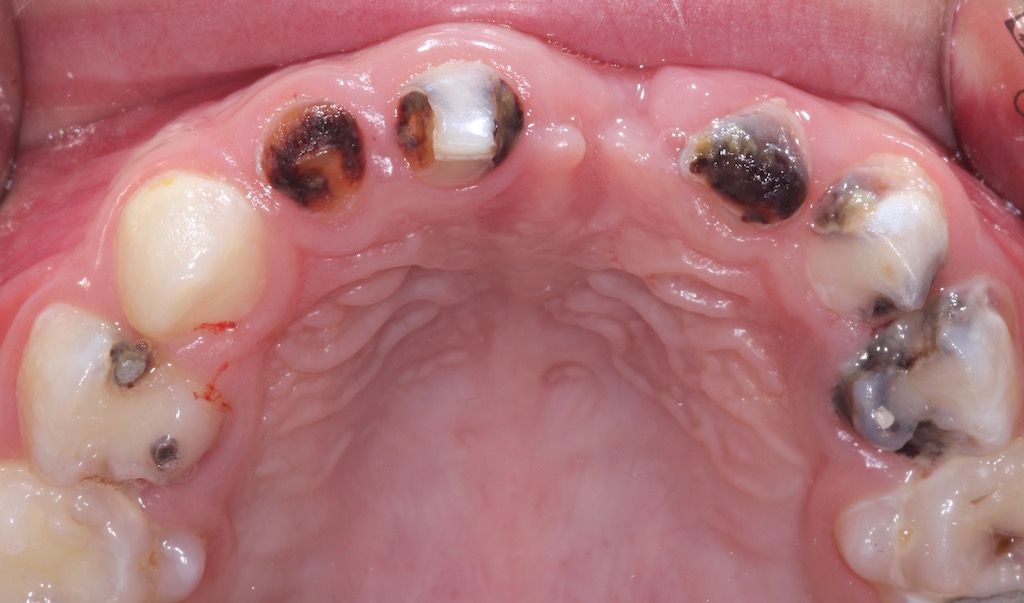

Example: The picture shows a so-called "early childhood caries" (ECC) with numerous carious lesions in the deciduous teeth. Due to the urgent treatment need, the high degree of tooth destruction and the patient's age, treatment under intubation anaesthesia is indicated.